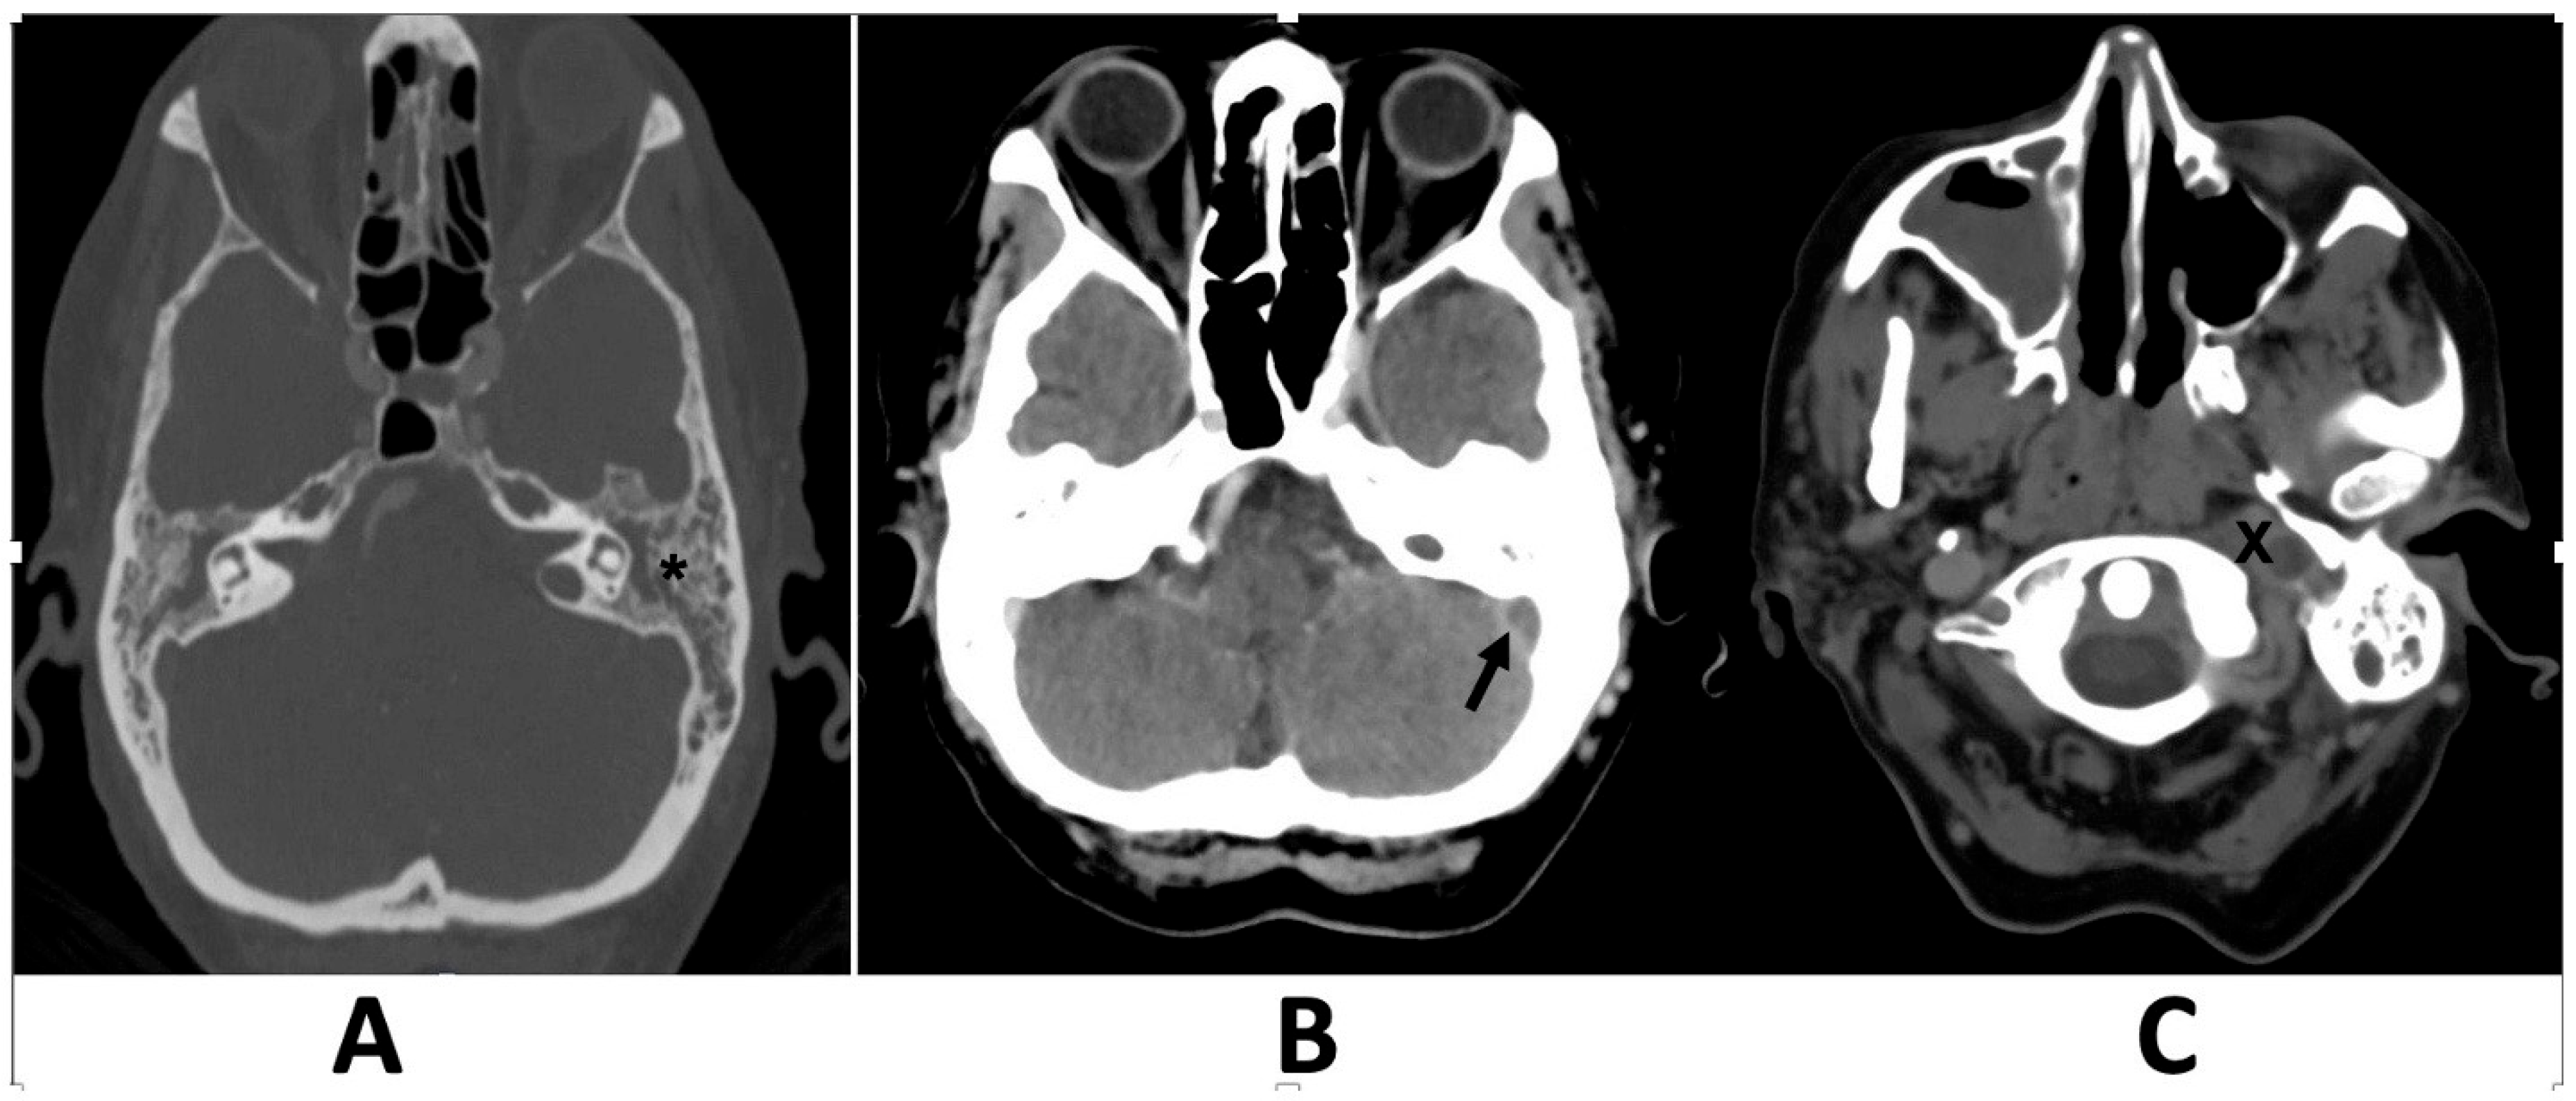

Fusobacterium necrophorum. High-resolution computed tomography (CT) of the left ear revealed coalescent mastoiditis and complete middle ear opacification without erosion of the mastoid septa (

Figure 1).

After contrast administration, the left jugular bulb and sigmoid sinus were not opacified, suggesting acute thrombosis at the proximal end of the jugular vein and sigmoid sinus. Brain and skull base magnetic resonance imaging (MRI) and magnetic resonance venography (MRV) confirmed temporal bone inflammation, sigmoid sinus thrombosis extending to the internal jugular vein, jugular vein thrombophlebitis, and no other intracranial complications (

In such cases, contrast-enhanced computed tomography (CT) is the primary diagnostic modality. Although magnetic resonance venography (MRV) is not crucial for diagnosing vein thrombosis, it helps determine the extent of the thrombotic process and monitor the progress of anticoagulation therapy. Additionally, magnetic resonance imaging (MRI) scans were performed on patients showing clinical symptoms or CT findings suggestive of intracranial complications, as the MRI has proven to be more sensitive in detecting these issues.